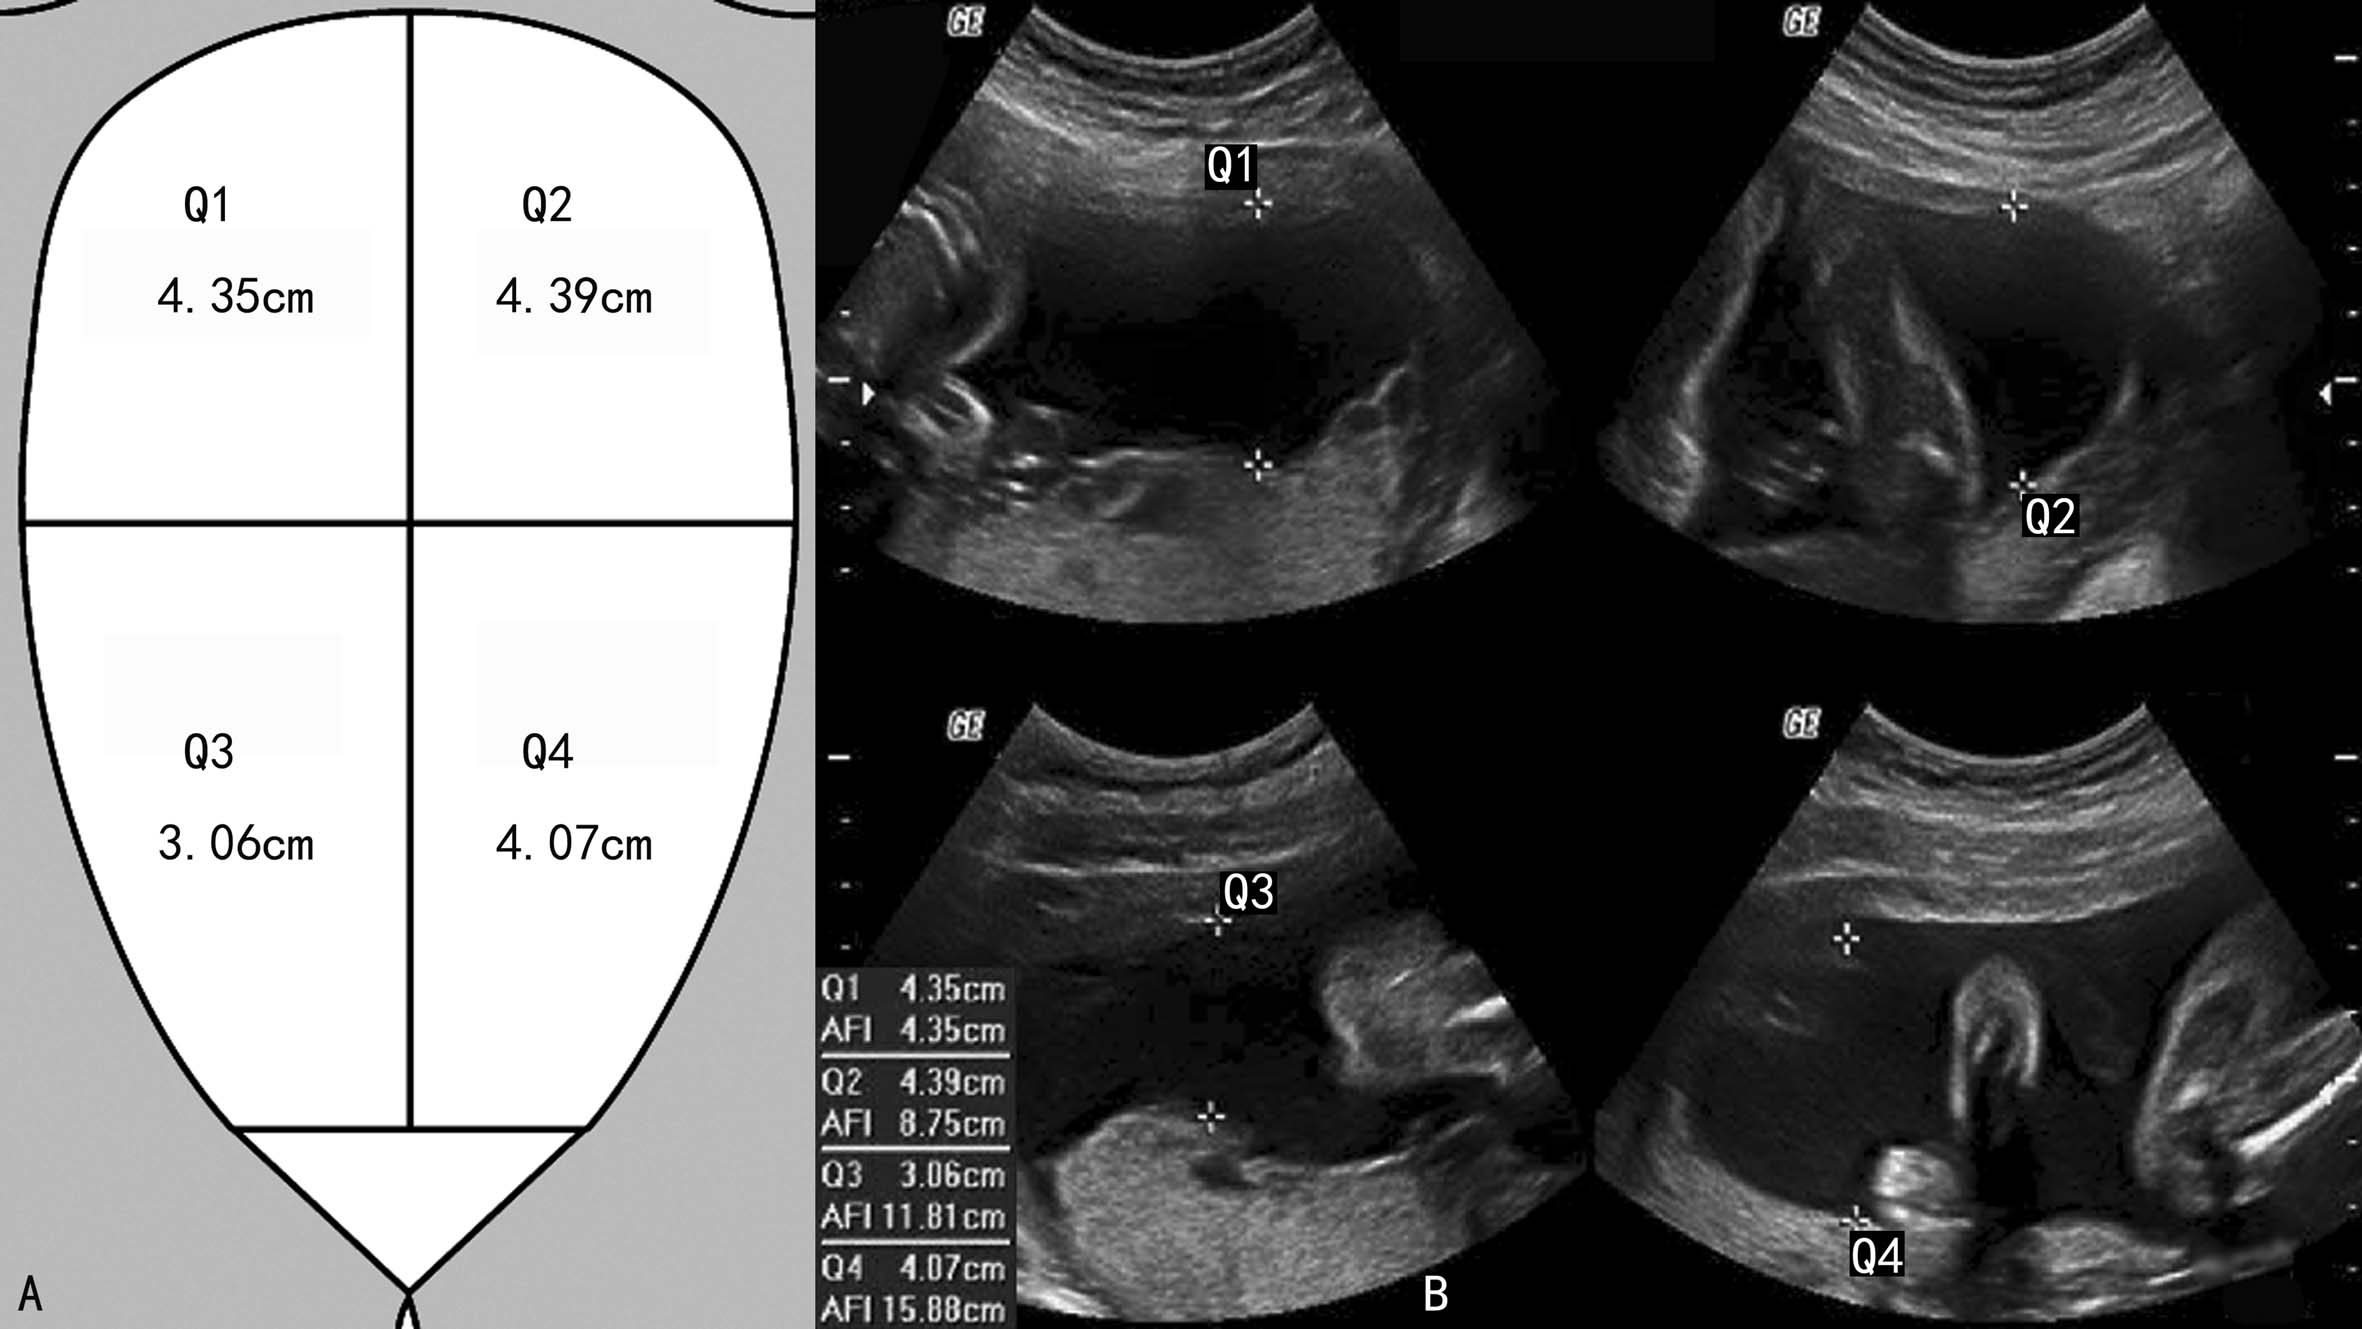

3.羊水指数法 将妊娠子宫的体表投影分为四个象限,测量四个象限内最清晰的羊水池内径,将测得的数值相加获得的和称为羊水指数(AFI) (图4)。测量时应当注意避开充满胎儿肢体或脐带的区域,但如果仅包含部分胎儿肢体或脐带则可以用做测量区。

图11-14羊水指数评估羊水量

正常时羊水指数为8~22cm。

使用羊水指数评估羊水量,不同的研究者有不同的定义。研究者将AFI与染色法评估羊水量进行比较,也得出了不同结论;以不同的AFI分组,5.1~8.0cm和8.0~20cm组,胎儿心率异常和因胎儿宫内缺氧剖宫结束妊娠的比例无显著差异。有笔者试图以AFI法和MVP测量法结合使用评估羊水量,但并没有提高羊水定量的准确性。